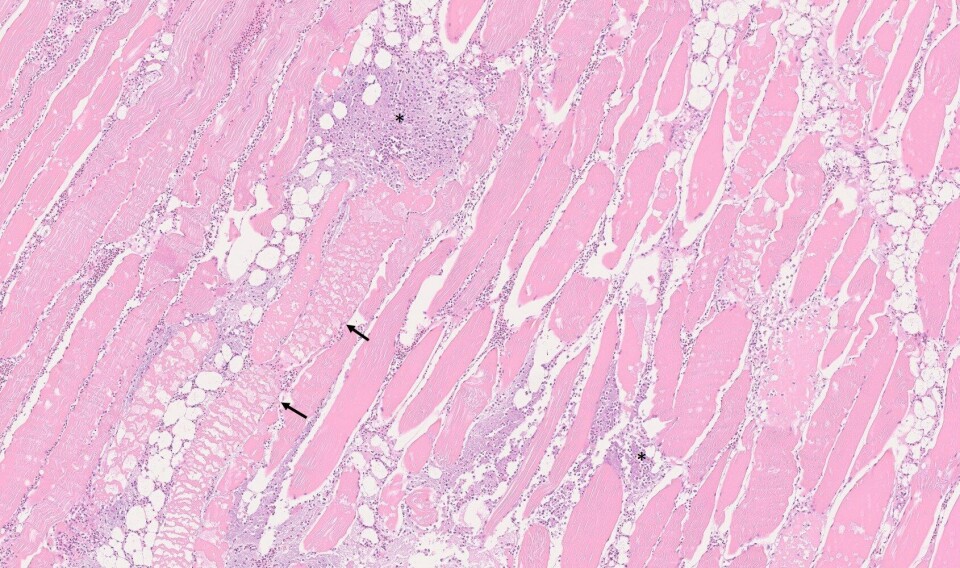

Skjelettmuskel med omfattende betennelse og infiltrasjon av pasteurella-bakterier (stjerne). Fokal degenerasjon av hvit muskel (pil). Foto: Veterinærinstituttet